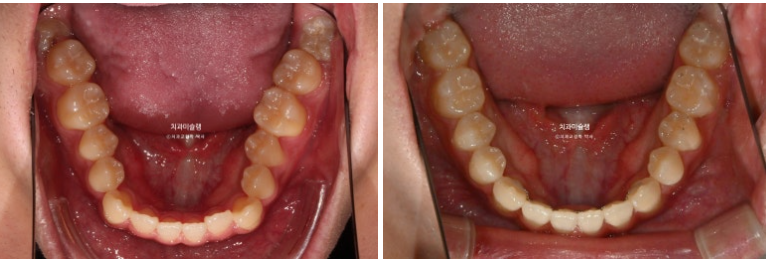

치료계획은 아래 사랑니 2개를 발치하고 사랑니 공간으로 치열을 뒤로 미는 것 입니다.

아래 앞니는 아래턱뼈 치조골 한계가 허용하는 극한까지 뒤로 들어갔습니다.

아래 어금니들은 가용한 사랑니 공간을 최대한 이용하며 뒤로 들어갔습니다.

2년 반동안 치근흡수도 없고 치근평행도는 좋습니다.